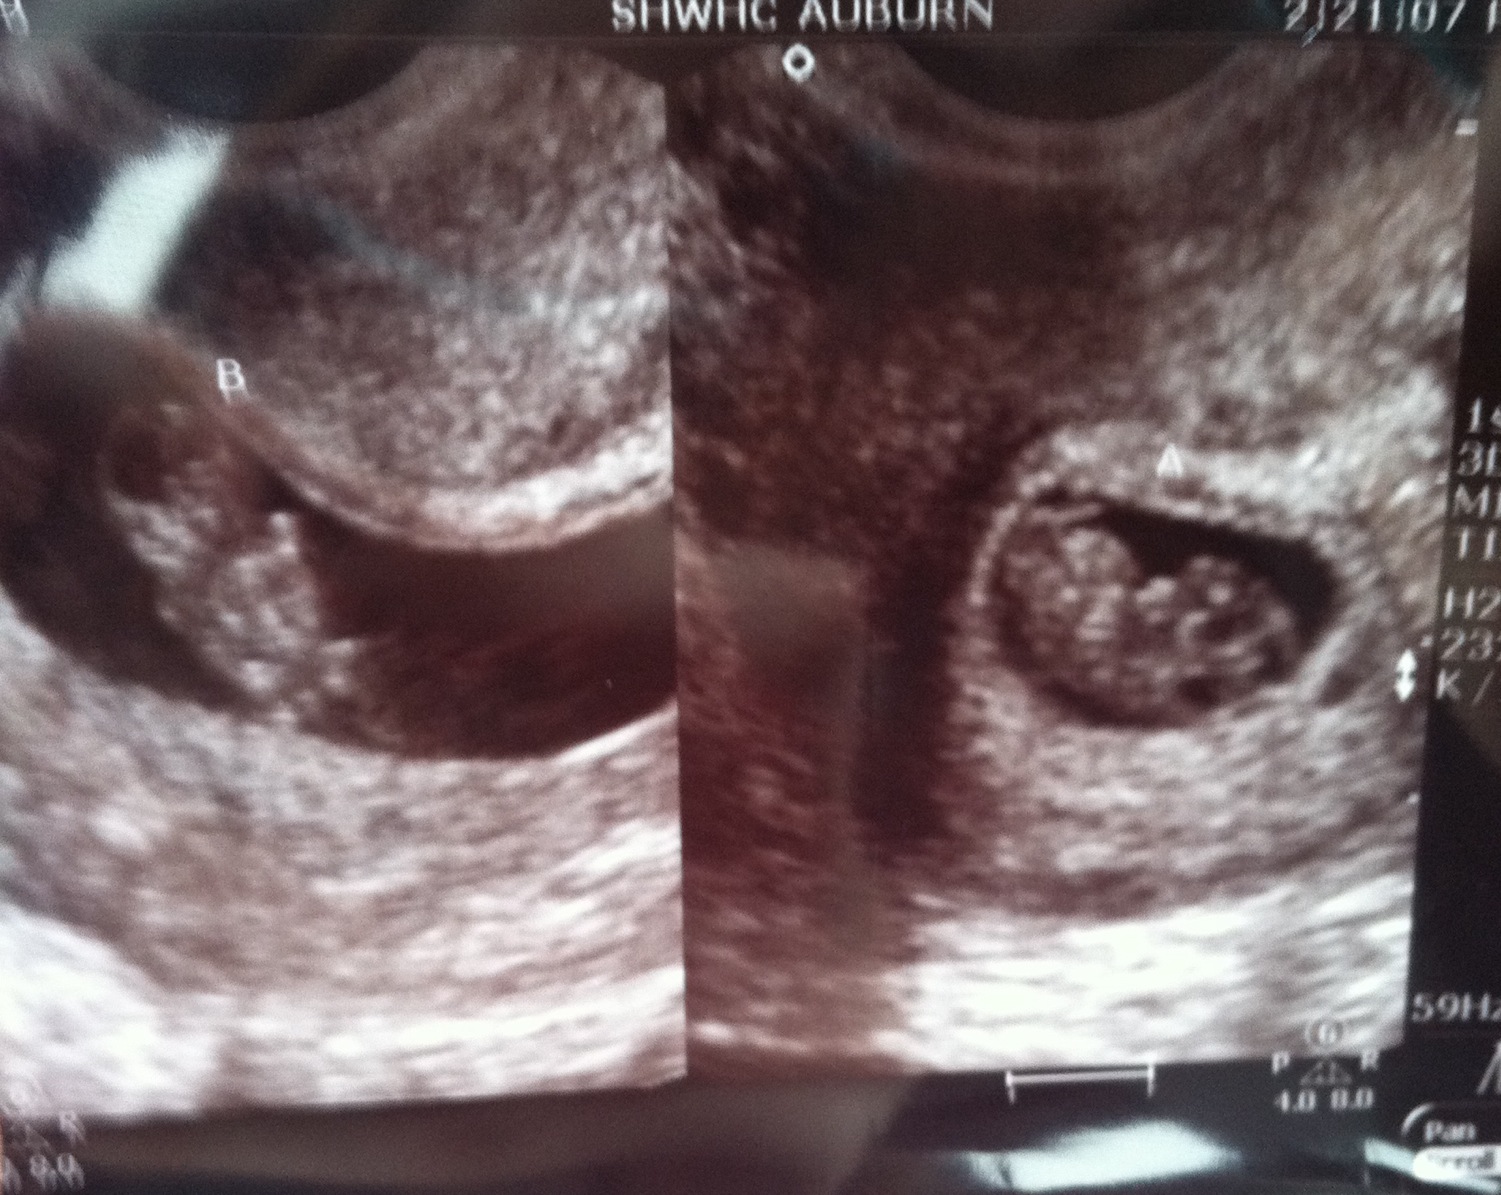

Still in shock here. Had our first appointment yesterday, which they told us was just for a pelvic exam and blood work. Well my uterus was tilted so the doctor opted to do an ultrasound. The ultrasound tech told us to hold our breath...there's two! They think they're identical, and we weren't doing any fertility treatments. So this was QUITE unexpected, but we're very excited!